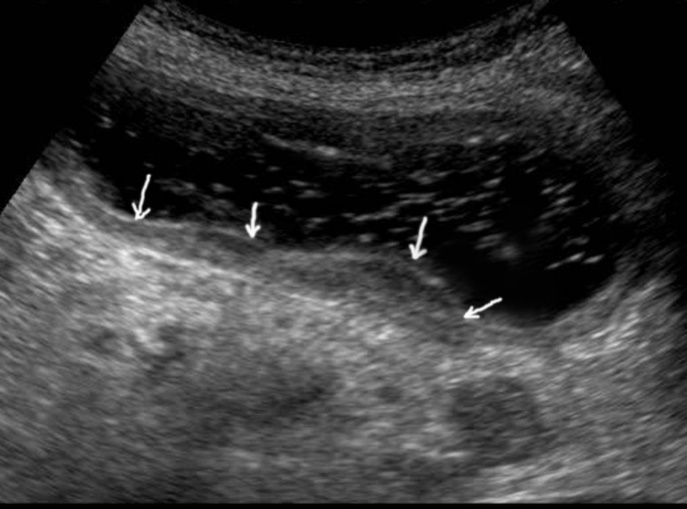

TAS of an empty stomach visualizes only the abdominal part of the esophagus which is 3-4 cm long. In the center of the esophagus, the mucosa of both walls is well defined as a thin hyperechoic linear structure. The walls of the unchanged esophagus have a linear layered structure (Figure 1).

Figure 1.Ultrasonography of the abdominal esophagus (vertical arrows). Horizontal arrow shows mucosa of the esophagus